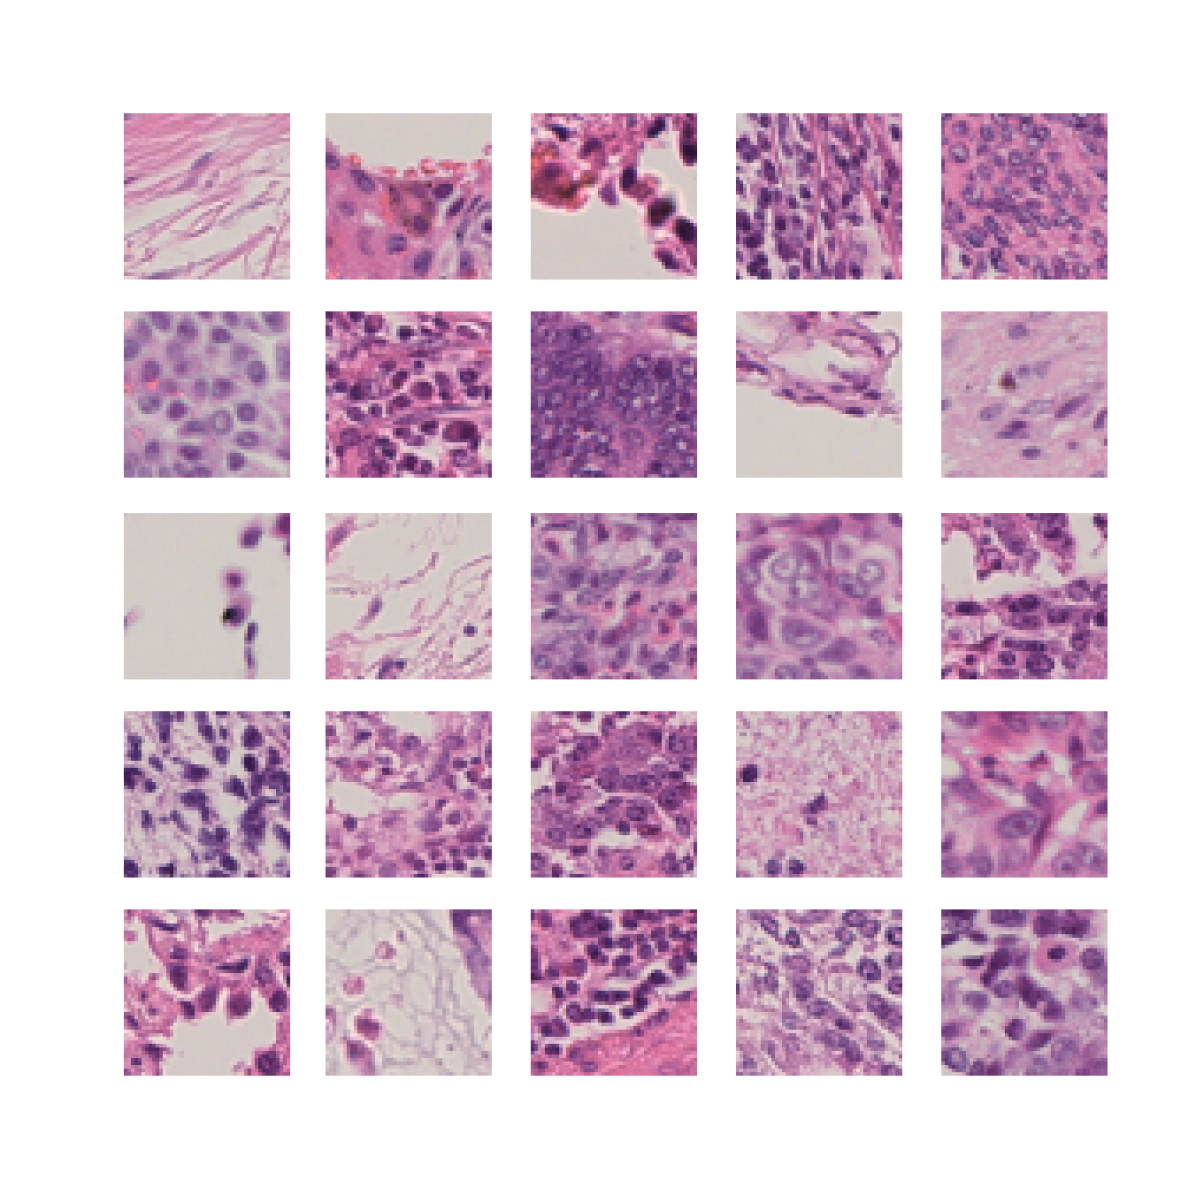

We also analyse the activation maps for each model using GradCAM as described in section S3. This offers more insight into the areas of the image which are contributing most heavily to the models’ representations. In Figure 4(b) we present some representative examples, however, a larger selection which was chosen at random is presented in Figures S10 to S25. The larger selection makes it easier to see the emergent patterns, including that privileged Siamese models tend to mainly identify features which are strongly present in both inputs, while unprivileged Siamese models tend to learn more diffuse features that are not specific to one cell phenotype or image region. TriDeNT ♆ incorporates both sets of features, learning both features specific to the privileged data and more the general features associated with unprivileged Siamese networks.

We can see in Figure 4(b) panel A that for ERG, the privileged Siamese model focuses almost exclusively on any nuclei which could be endothelial cells. As there are very few endothelial cells in the dataset, it could be an effective strategy to identify anything that could potentially be an endothelial cell to minimise the difference between the representations of the H&E model and the IF mask model. In the corresponding unprivileged Siamese image, we see that the model identifies some of these nuclei, albeit less strongly, but also focuses heavily on the other tissue and even the background, while strongly fixating on two spots of debris in the center of the image. This model has less ‘incentive’ to learn the weak features related to endothelial cells as these occur rarely and are not easy to detect, while more generic strong features such as the presence of connective tissue and the prevalence of background are more common and predictable from augmented images. We see that TriDeNT ♆ combines these two feature sets, strongly identifying nuclei while also identifying the connective tissue.

In panel C we see a similar pattern, with the privileged Siamese model fixating solely on the nuclei, while the TriDeNT ♆ model takes a more balanced approach. The unprivileged Siamese model appears to focus on a single cluster of nuclei while neglecting others, and similarly identifies an area of fibroblasts with its distinctive pattern but does not others.

In contrast to panels A and C which represent models with poor privileged Siamese results, panels B and D represent models whose privileged Siamese results were comparable to both TriDeNT ♆ and even the supervised baseline. It is therefore interesting to note that there are far more similarities between the privileged Siamese and TriDeNT ♆ models in both cases. Particularly in panel B, TriDeNT ♆ and the privileged Siamese model return virtually identical heatmaps, with both strongly identifying epithelial nuclei and neglecting the same areas of connective tissue. The unprivileged model in this case appears to focus solely on the centre of the image, giving a significantly different heatmap to the other panels.

Panel D again shows the previous pattern, with the privileged Siamese model identifying the features strongly present in the privileged data – fibroblasts – while neglecting the nuclei present. TriDeNT ♆ also strongly identifies the connective tissue, but, unlike the privileged Siamese model, does not completely neglect the nuclei. The unprivileged Siamese model primarily identifies background, and does not appear to identify the nuclei in this example.